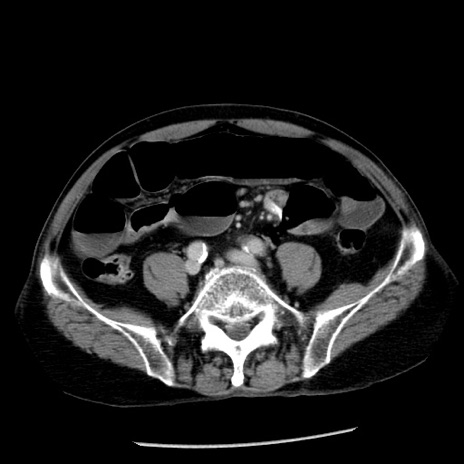

症例26(横断像)

【症例】80歳代男性

【主訴】嘔吐

【現病歴】昨晩2回嘔吐あり、今朝になっても嘔吐あり。来院。

【既往歴】胃潰瘍

【身体所見】意識清明、BT 37.6℃、BP 166/95mmHg、HR 100bpm、SpO2 97%、腹部:平坦・軟、腸蠕動音聴取良好、圧痛なし。

【データ】WBC 21900、CRP 1.46